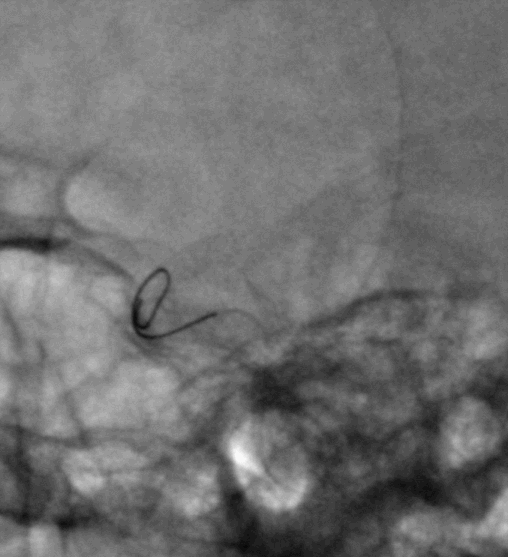

脑血管造影提示右侧颈内动脉颅内段多发动脉瘤(反主动脉弓)

脑血管造影提示右侧颈内动脉颅内段多发动脉瘤

4mm×30mm Streamline

术后4月余随访:多发动脉瘤均未见显影,远端残余轻度狭窄

术前术后对比